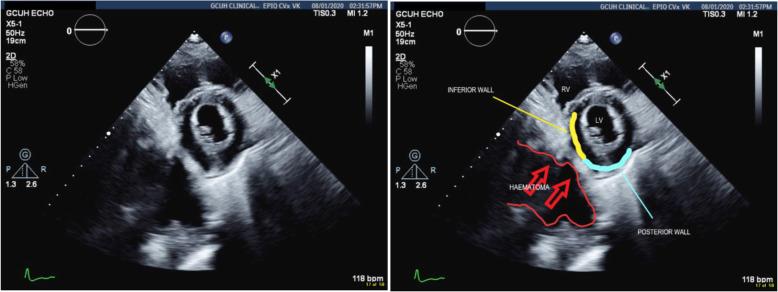

There exists a therapeutic conflict between haemorrhage control and prevention of thromboembolic events following polytrauma and complications are not uncommon. Such opposing therapies can result in unexpected pathophysiology and there is a real risk of misdiagnosis resulting in harm. This case presents a previously unreported complication of prevention and management of thromboembolism- STEMI (ST elevation myocardial infarction) and tamponade mimic secondary to retroperitoneal haematoma.

CASE PRESENTATION

We present a 50-year-old male polytrauma patient who following treatment for presumed pulmonary embolus demonstrated classical clinical findings of myocardial infarction and pericardial tamponade secondary to a retroperitoneal haematoma. This is an event not previously reported in the literature. The risk of adverse outcome by management along the standard lines of STEMI (ST elevation myocardial infarction) was averted through awareness for alternative aetiology via a multi-team approach which resulted in percutaneous drainage of the haematoma and complete resolution of symptoms.